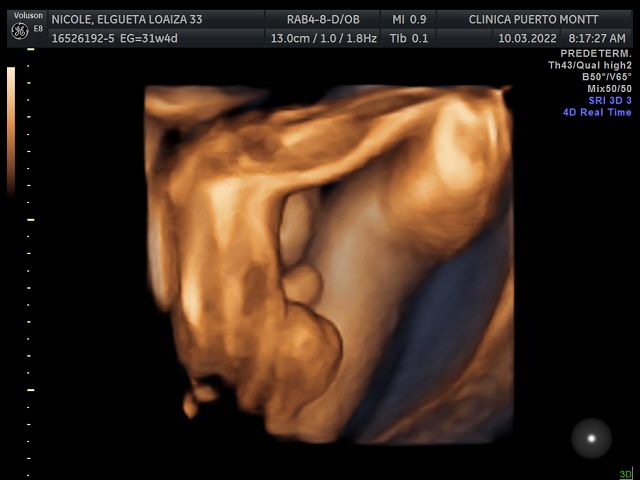

Ecografia Obstetrica y ginecologia

Ecografia volumétrica (3 D y 4D)

Ecografía 4D 90000 $

Ecografía fetal 50000 $